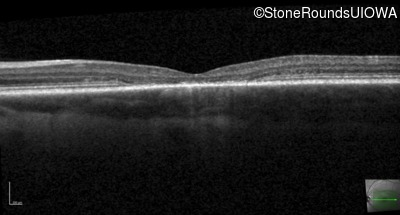

Optical Coherence Tomography - Left - 20/80

Exemplar / OCT Stack

OCT Stack